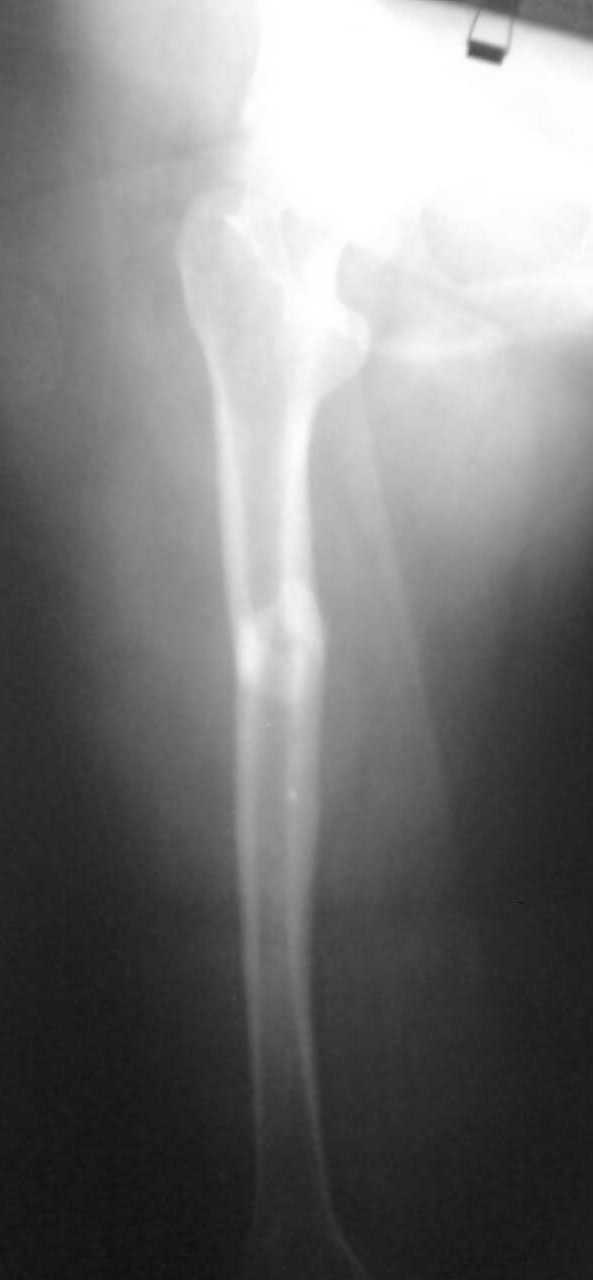

[Ortho] перелом бедренной кости

дополнительные снимки

Имя     : Фото075.jpg